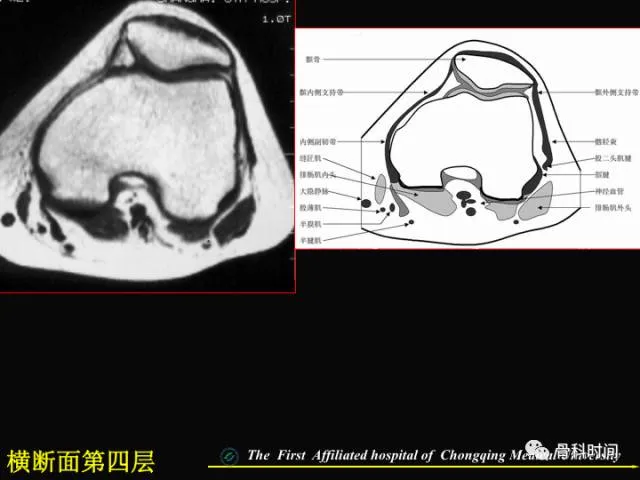

你知道半月板损伤的 MRI 是如何分级的吗?半月板撕裂的 MRI 表现又是怎么样的?

今天给大家分享一份精美 PPT,全方位详述膝关节半月板 MRI 的要点,一起来学习一下: